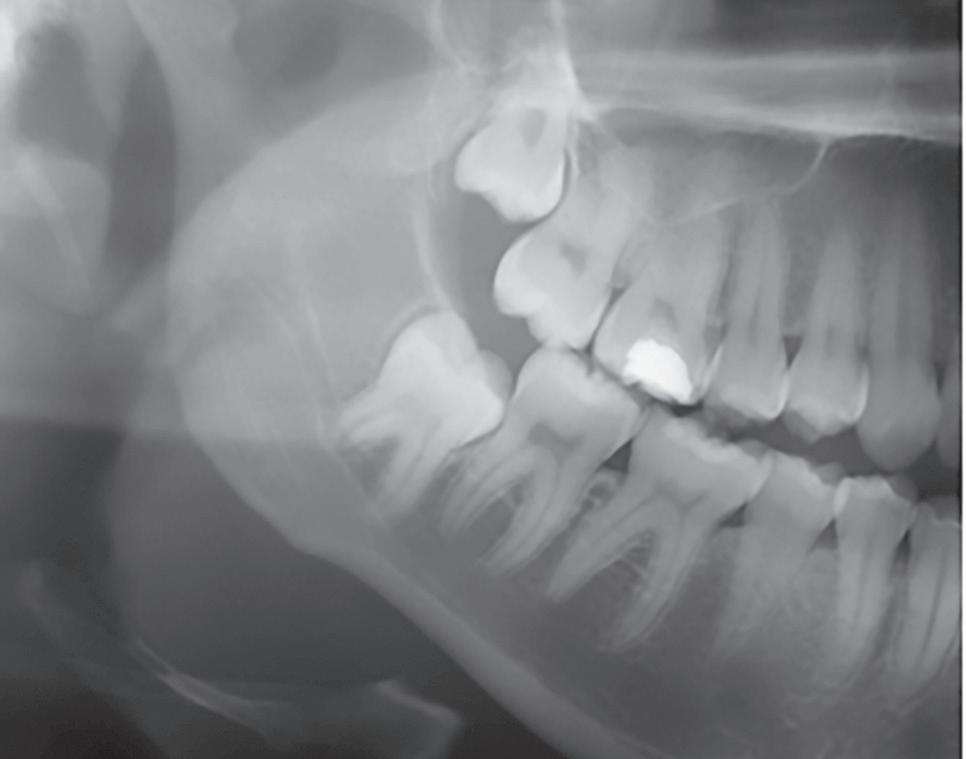

For data collection, a questionnaire was designed including age, gender, title (resident/specialized, specialist, master, doctor), training time in the field and a series of four hypothetical clinical cases on which each professional evaluated radiographic images with different types of dental impactions in the mandible and expressed indication or not for extraction (Fig 1). The radiographic images were obtained from the database of a radiology clinic in Recife/PE.

Sixty-four percent opted to remove the impacted tooth as a prophylactic measure, since most cases presented were young patients. However, the percentage of indication for extraction varied according to the clinical situation presented. The total of indications per case is observed in Table 1.

A

B

C

D

Figure 1: Radiographic images to assess the extraction of the impacted lower third molar: A) young patient without comorbidities, asymptomatic (case 1); B) elderly patient without comorbidities, asymptomatic (case 2); C) young patient without comorbidities, asymptomatic (case 3); D) young patient without comorbidities, asymptomatic (case 4).